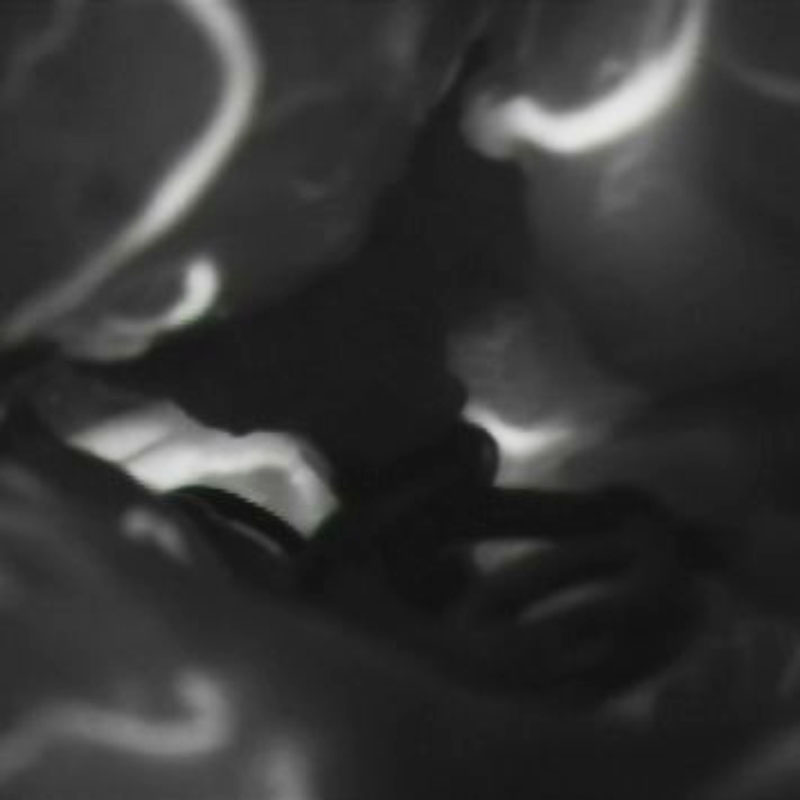

4

'25年1月

40代

右中大脳動脈瘤

クリッピング術

手術前

クリップ前

クリップ後

術後血管撮影